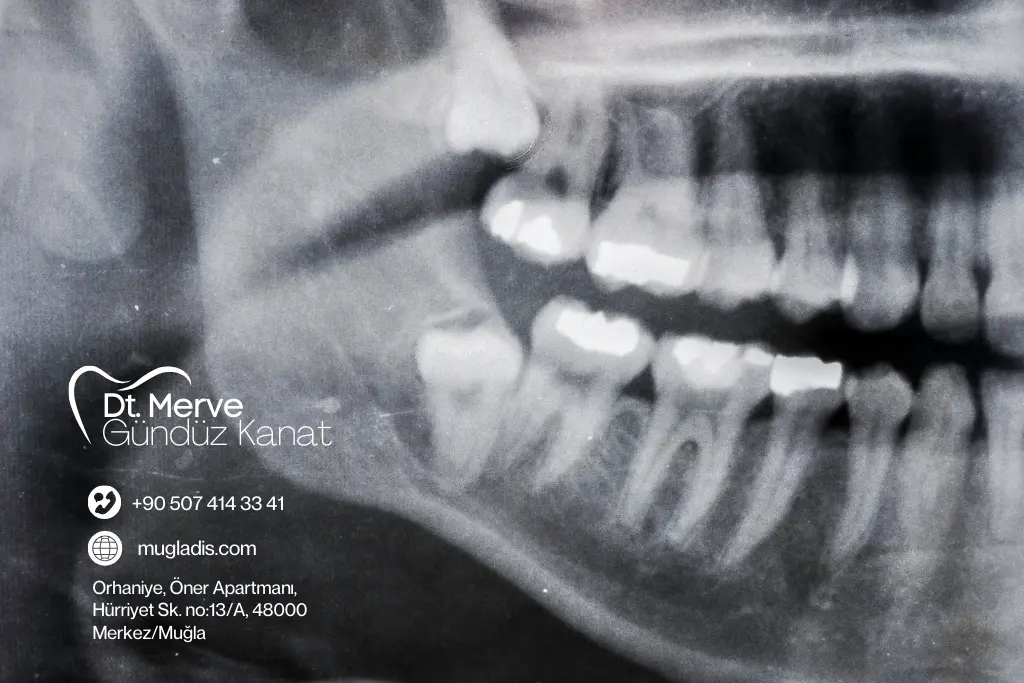

Muğla Menteşe’deki diş kliniğimizde, 20’lik diş çekimi işlemini güvenli ve konforlu bir şekilde gerçekleştiriyoruz. Öncelikle, dişlerinizin konumunu panoramik röntgen ile detaylı olarak inceliyor ve size en uygun tedavi planını hazırlıyoruz. Ardından, dişin durumuna göre normal çekim ya da cerrahi yöntemle işlemi uyguluyoruz. Lokal anestezi sayesinde çekim sırasında ağrı hissetmiyor, süreci rahat geçiriyorsunuz. Son olarak, iyileşme sürecini hızlandırmak ve konforunuzu artırmak için size özel bakım önerileri sunuyoruz. Böylece, ağız sağlığınızı koruyarak daha rahat bir yaşam sürmenizi sağlıyoruz.

Muayene ve Değerlendirme

Dişlerinizin konumu incelenir ve kişiye özel çekim planı hazırlanır.